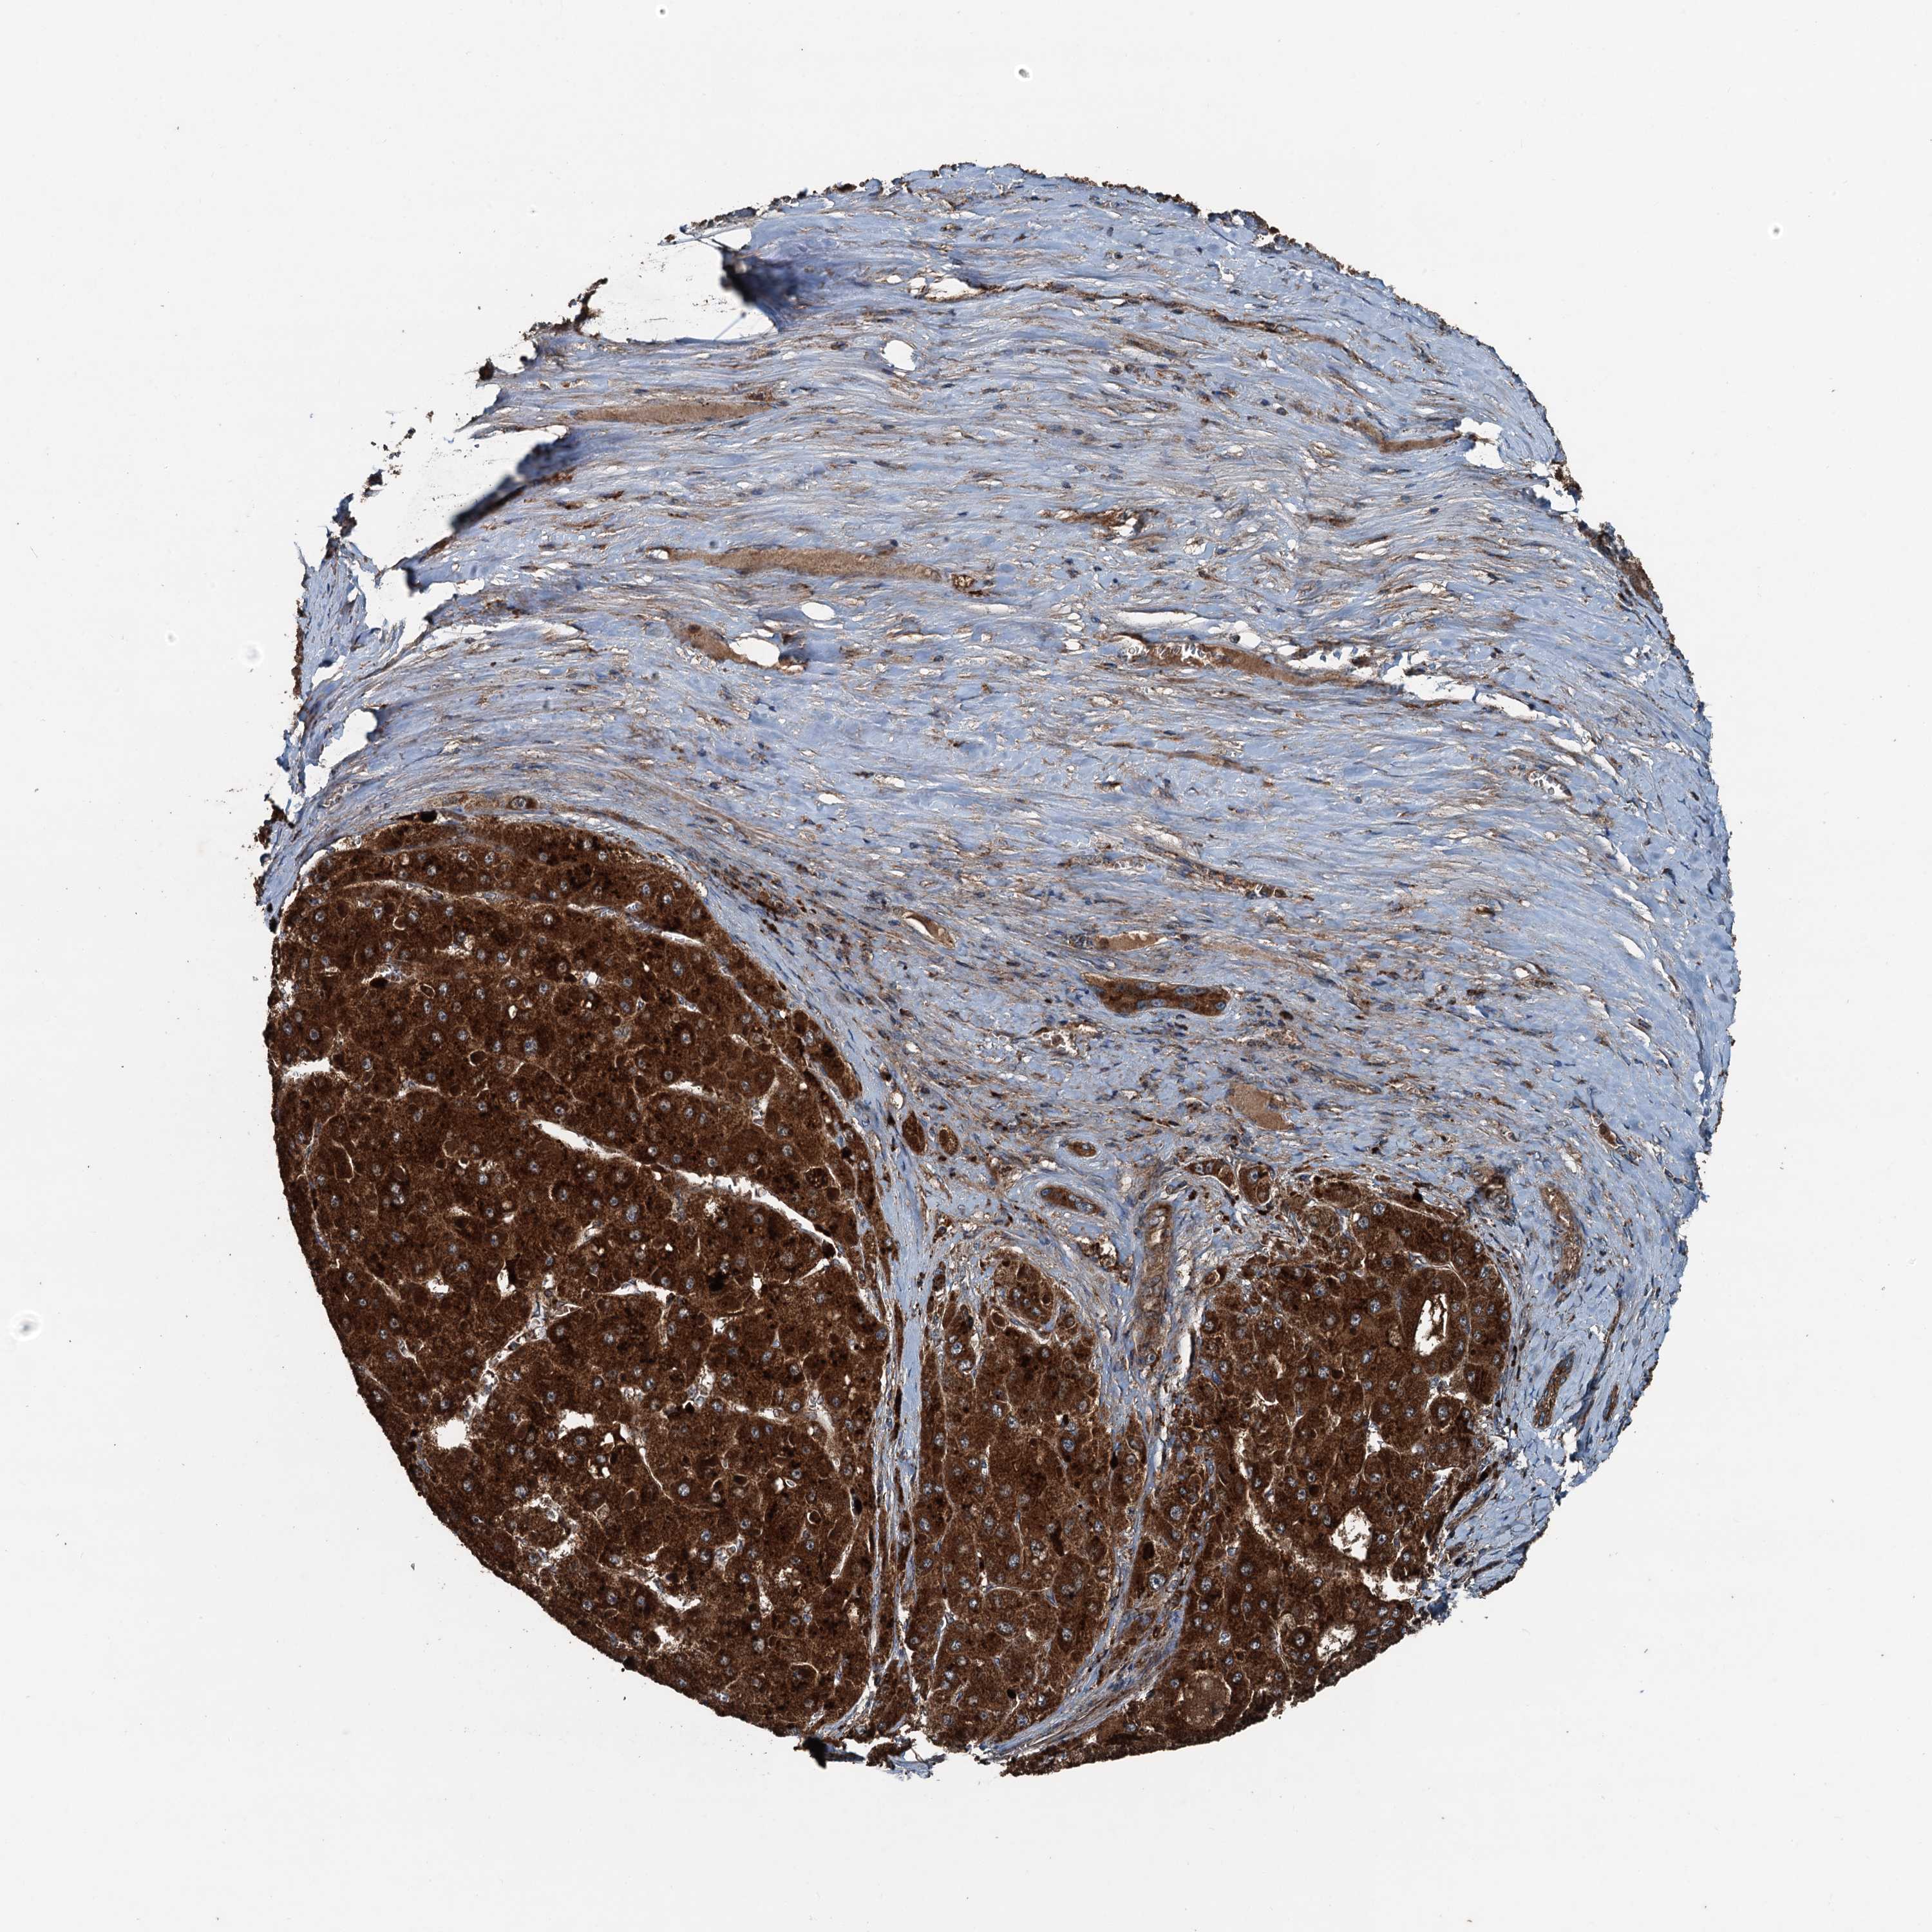

LIVER CANCER - Protein expressioni

A mouse-over function shows sample information and annotation data. Click on an image to view it in a full screen mode. Samples can be filtered based on level of antibody staining by selecting one or several of the following categories: high, medium, low and not detected. The assay and annotation is described here.

Note that samples used for immunohistochemistry by the Human Protein Atlas do not correspond to samples in the TCGA dataset.

Antibody stainingi

Antibody staining in the annotated cell types in the current human tissue is reported as not detected, low, medium, or high, based on conventional immunohistochemistry profiling in selected tissues. This score is based on the combination of the staining intensity and fraction of stained cells.

Each image is clickable and will lead to virtual microscopy that enables deeper exploration of all samples and also displays staining intensity scores, fraction scores and subcellular localization as well as patient and tissue information for each sample.

Antibody HPA041227

Staining

High

Medium

Low

Not detected

Intensity

Strong

Moderate

Weak

Negative

Quantity

>75%

75%-25%

<25%

None

Location

Nuclear

Cytoplasmic/membranous

Cytoplasmic/membranous,nuclear

Cholangiocarcinoma

Carcinoma, Hepatocellular, NOS